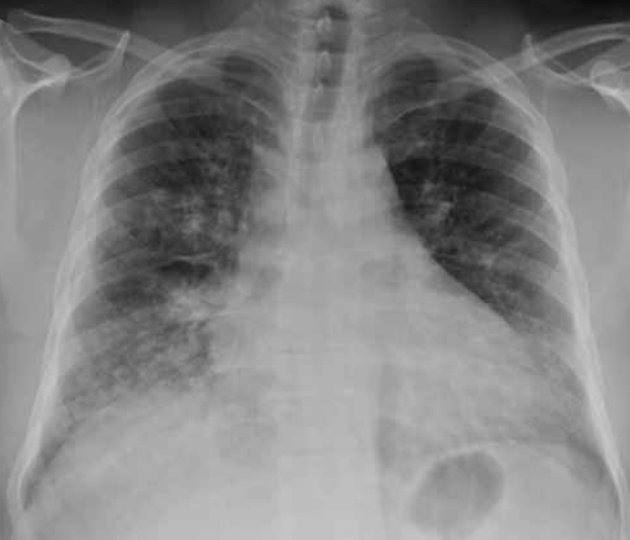

51

Hemorragia pulmonar bilateral. Aunque la placa de tórax puede resultar útil para el diagnóstico de hemorragia pulmonar, el contexto clínico es fundamental ya que los hallazgos radiológicos son indistinguibles del edema alveolar o de la neumonía. Las radiografías seriadas obtenidas durante varios días tras el episodio de hemorragia pulmonar aguda muestran un cambio de patrón progresivo: los primeros días se observan densidades alveolares difusas con broncograma aéreo de predominio bibasal o perihiliar. La resolución es rápida, mostrando un patrón reticular a los 2 o 3 días que va disminuyendo gradualmente hasta que la radiografía se normaliza por completo en torno a las 2 semanas.